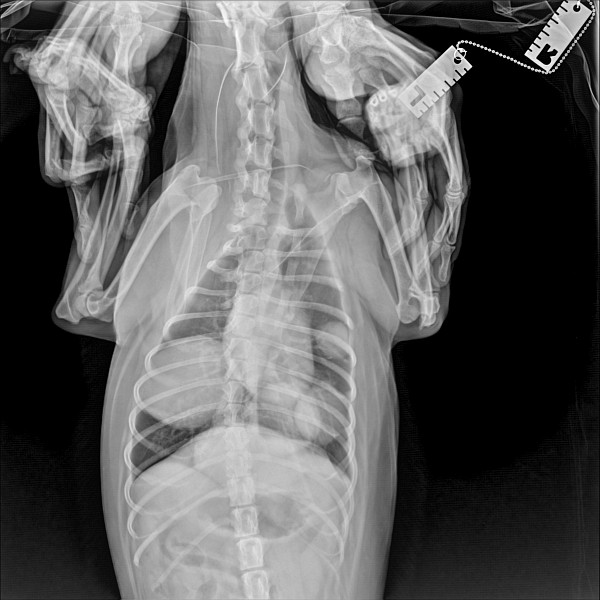

Добрый вечер! Можно ли по этим снимкам определить онкологию легких? Спасибо